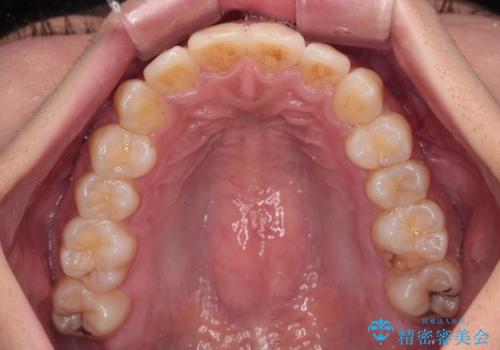

前歯のデコボコと隠れてしまう下顎前歯 インビザラインですっきりと改善

- 前歯のデコボコと、深い咬み合わせにより前歯が隠れていることを気にして来院された患者様です。

海外に長期滞在する予定があるとのことで、インビザラインにて矯正治療を行うこととしました。

インビザライン発注後に長期滞在先から2年間ほど帰国することができず、インビザラインの有効期限内に終了できるのか不安でしたが、矯正治療開始後は十分な装着時間を達成され、1年未満の期間で無事に終えることができました。